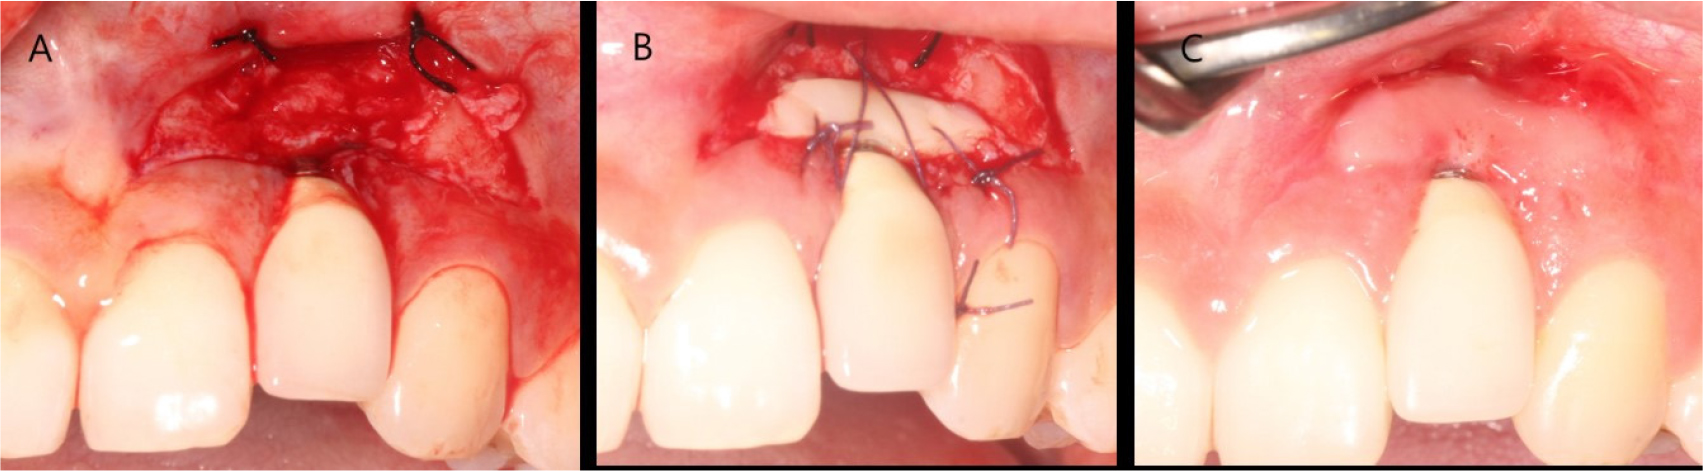

The patient was diagnosed with facial peri-implant soft tissue deficiency of the right maxillary lateral incisor. Soft tissue grafting was planned for gingival coverage of the exposed abutment. An intra-sulcular incision was made, and the flap was reflected. A bone dehiscence defect due to buccal bone resorption was observed. The exposed fixture was decontaminated using chlorhexidine ball scrubbing, titanium curettage and scaling, and saline irrigation. Subepithelial connective tissue was obtained from the palate using the trap door technique. Subepithelial connective tissue grafting was performed with a coronally advanced flap (Fig. 2).

The stitches were removed after 2 weeks. Normal healing took place without any adverse events. Complete abutment coverage did not occur, but the gingiva was thickened through soft tissue augmentation (Fig. 3). At the 3-year follow-up, gingival creeping had occurred. Furthermore, the fixture was not visible because the buccal gingiva had thickened, and peri-implant tissues had remained healthy (Fig. 4).